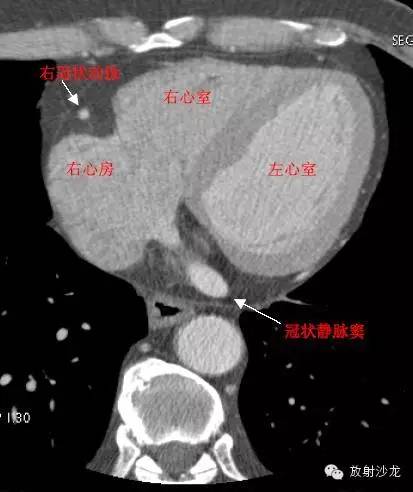

RA -Right Atrium右心房

LV -Left Ventricle左心室

RV -Right Ventricle右心室

RCA -Right Coronary Artery 右冠状动脉

RAA –Right AtrialAppendage右心耳

CS -Coronary Sinus冠状窦